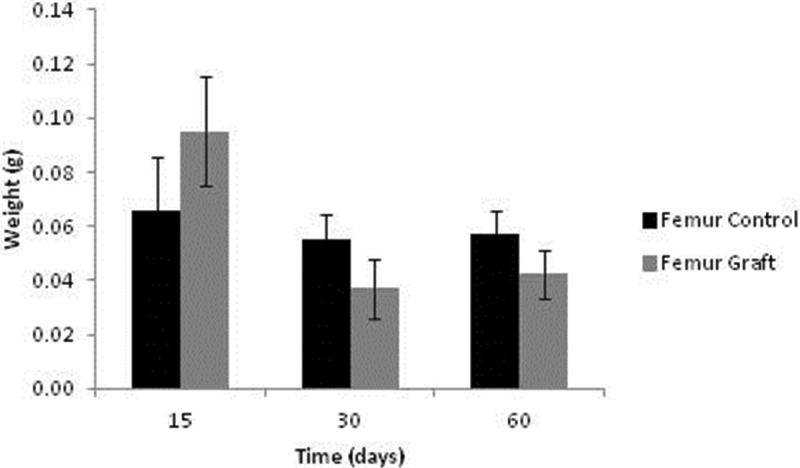

Bone weight data are presented in Figure 5. After 15 days, the grafts were heavier than the controls (p=0.038); however, these profiles were reversed after 30 and 60 days of implantation (p=0.035 and p=0.047, respectively).